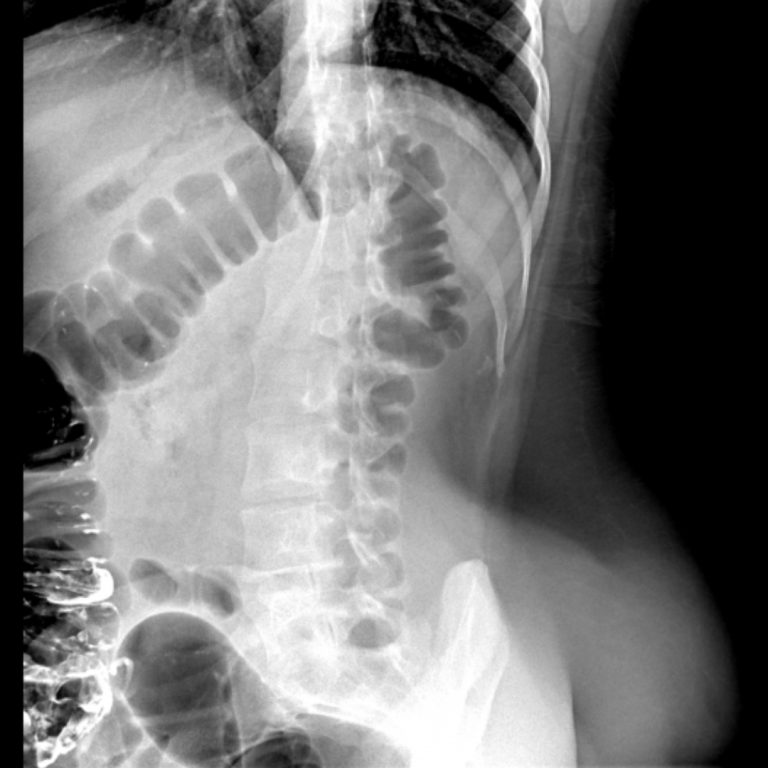

MİDE GRAFİSİ

Miğde grafisi, üst gastrointestinal sistemdeki sorunları teşhis etmek ve değerlendirmek amacıyla kullanılan bir tıbbi görüntüleme testidir. Bu test, hastanın mide içeriğini, mide duvarının yapısını ve mide hareketlerini görsel olarak incelemeyi sağlar.Miğde grafiği çekimi için öncelikle hastaya kontrast madde verilir. Kontrast madde , mideye giriş yaparken ve mide içerisinde dağılırken röntgen cihazıyla çekilen görüntüler alınır.